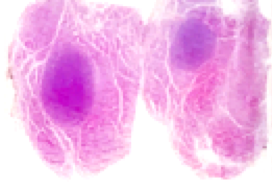

Veja esse exemplo:

Essa foto é parte do meu acervo de casos que foram sequenciados durante meu mestrado. Observe como o tumor representa uma pequena área da lâmina, e que a maioria do tecido é um parênquima sem alterações. Se cortamos esse bloco e levarmos diretamente para a extração, teremos o DNA tumoral e o DNA das outras células não neoplásicas misturados.

Estaríamos gerando uma “contaminação” com DNA não neoplásico e isso diminuirá a sensibilidade da detecção das mutações. Uma forma simples de entender, seria pensar que ao extrair todo o conteúdo da lâmina, sem macrodissecar, estaríamos “diluindo” o DNA tumoral antes de leva-lo ao sequenciamento.